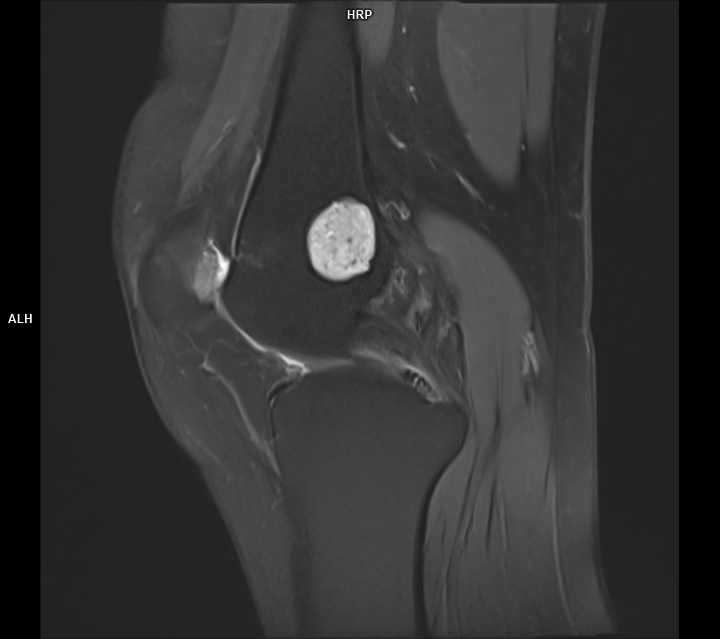

CAZ nr 44 Encondrom femural distal

Figura 1: achiziție în plan coronal în ponderație PD cu saturația grăsimii

Discuție caz nr 44: Encondromul este o tumora benignă cu origine cartilaginoasă; cazul prezentat evidențiază o leziune net delimitată în hipersemnal PD, hiposemnal T1, fără restricție de difuzie, ce nu modifica semnalul țesutului osos de vecinătate si se dezvoltă de o parte şi de alta a cartilajului de creștere.